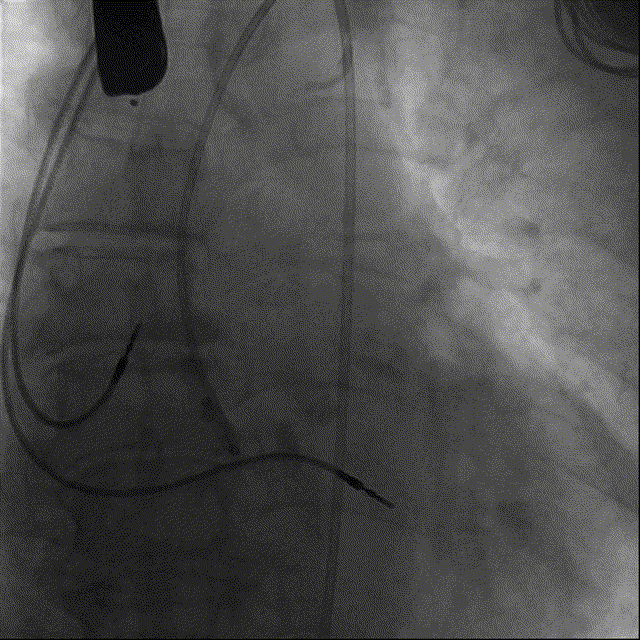

主动脉根部造影

22mm球囊预扩